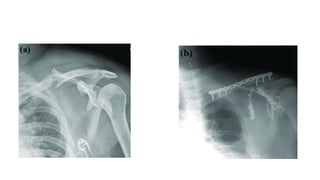

SURGICAL MANAGEMENT

• Fix both (goss)

• Some authors feel if clavicle fixed it may be enough

• However if scapular fracture remain displaced it should be fixed

• Sequence of fixation has to be individualised

Operative management : Clavicle plating 1st

: scapula still unreduced

:scapula fixation – undisplace #